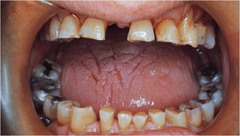

-generalized extensive destruction of tooth surface -meth use